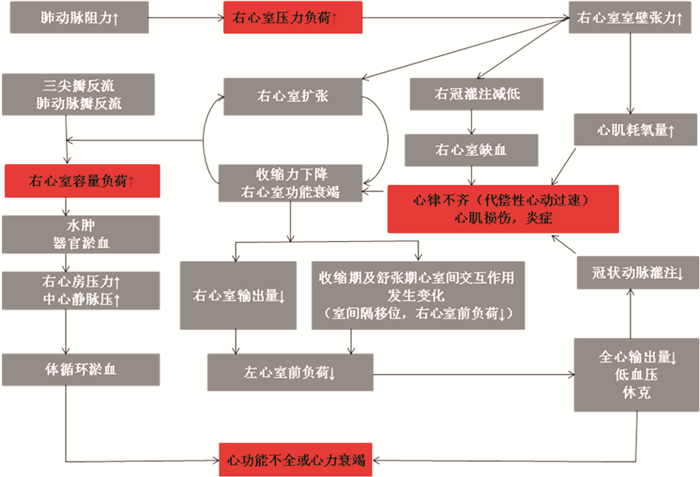

3 右心室功能评价方法 3.1 超声心动图经胸超声心动图可以反映肺动脉压力及继发右心室的结构改变。具有无创、可重复强、兼顾左心结构及功能等特点,有利于临床动态观察。超声心动图评价指标有右心室tei指数、三尖瓣环收缩期位移(tricuspid annular plane systolic excursion, TAPSE)、三尖瓣环收缩期峰值速度(tricuspid annular peak systolic velocity, TAPSV)、等容收缩期心肌加速度(isovolumic myocardial acceleration, IMA)、右心室面积变化分数(right ventricular fractional area change, RVFAC)、右心室射血分数(right ventricular ejection fraction, RVEF)、舒张早期E波峰值流速、晚期A波峰值流速及其E/A比值等。见图 5。

|

| 图 5 经胸超声心动图右心室短轴的正常状态及室间隔(the intraventricular septum,IVS)(a)及肺循环阻力升高后右心室急性舒张状态(b)时IVS呈现的D字型改变 |